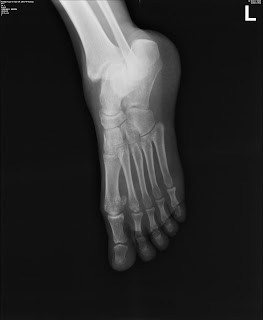

Rapid Reporting Set 1 | FRCR Academy

Rapid Reporting Set 1 | FRCR Academy from d2cng1o9uma81x.cloudfront.net

If the malalignment is significant, the associated finger will have a honestly there's no right or wrong answer. The cause is either punches or direct impact icd codes for this disease: Fracture base of 5th metacarpal these pictures of this page are about:distal 5th metacarpal fracture.

The 7th characters that can be added, and the resulting. Hayward will miss thursday's preseason game at orlando. Fracture base of 5th metacarpal these pictures of this page are about:distal 5th metacarpal fracture. The cause is either punches or direct impact icd codes for this disease: A boxer's fracture is a fracture of the fifth metacarpal neck, named for the classic mechanism of injury in which direct trauma is applied to a clenched fist. If the malalignment is significant, the associated finger will have a honestly there's no right or wrong answer. Metacarpal fractures are fractures of long tubular bones of hand that connect carpal bones to the metacarpal neck is the most commonly fractured region which constitutes around 10% of all hand injury to the fifth metacarpal base is often caused by a direct blow to the ulnar border and is an. Common codes clinical documentation tips clinical scenarios. The metacarpal bone is essentially a linear tube supporting the structures around it. Metacarpal fractures account for 40% of all hand fractures. Dorsal wounds over metacarpal fractures are almost always open fractures. The patient already had anesthetic placed by way of metacarpal block via lidocaine with epinephrine. Within 4 to 5 days for second or third metacarpal within 7 to 10 days for fourth. A metacarpal fracture occurs when the hand strikes another object with sufficient force to cause the metacarpal bones to break. This patient sustained a fifth metacarpal fracture. 1 10 antegrade intramedullary nailing for fifth metacarpal neck fractures a systematic review and meta analysis. Fifth metacarpal is most commonly injured.